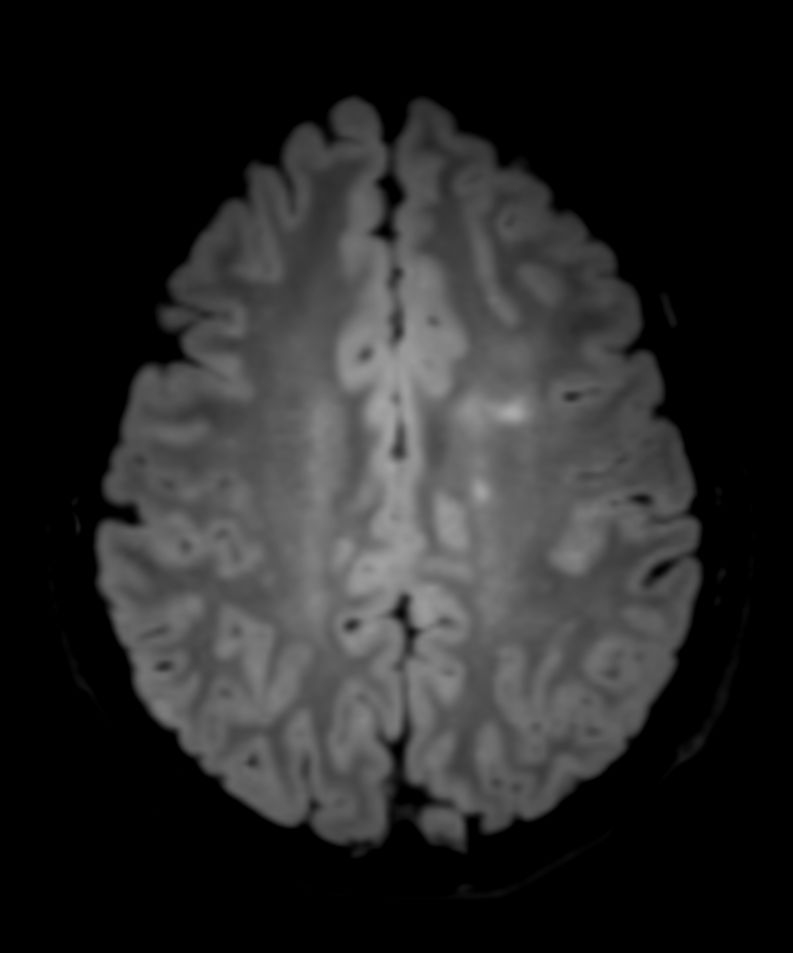

SWI sequence has a high sensitivity to enhance contrast for deoxygenated (venous) blood or calcium deposits. This may help, when used in combination with other clinical information, in the diagnosis of various neurological pathologies. 3D imaging lets you acquire high resolution data in multiple directions in one scan. Isotropic voxel size enables reformats in any plane without loss of resolution. FLAIR* requires offline post processing combining the contrast of 3D FLAIR and 3D SWI EPI into a single image. This enables the visualization of Central Vein Sign, mapping subcortical veins onto 3D FLAIR contrast images.